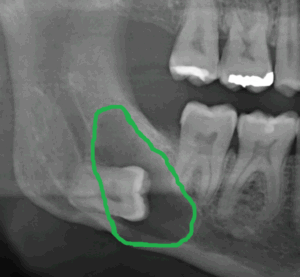

Weisheitszahn mit vorliegender Zyste – Auf dem ersten Röntgenbild liegt ein Weisheitszahn tief im Kiefer. Ausgehend vom Zahnsäckchen, das für die Zahnbildung erforderlich ist, hat sich eine Zyste an der Zahnkrone gebildet. Auf dem zweiten Röntgenbild ist zum besseren Verständnis die Zyste grün umrandet. Beim normalen Zahndurchbruch durch die Schleimhaut bildet sich das Zahnsäckchen zurück. Bei Zähnen, die im Kiefer verbleiben, kann sich, wie in diesem Fall, eine Zyste bilden und den Kiefer in seiner Stabilität schwächen. In diesen Fällen kann schon beim Kauen der Kiefer brechen. Eine rechtzeitige Entfernung solcher Zähne kann die genannten Risiken minimieren.